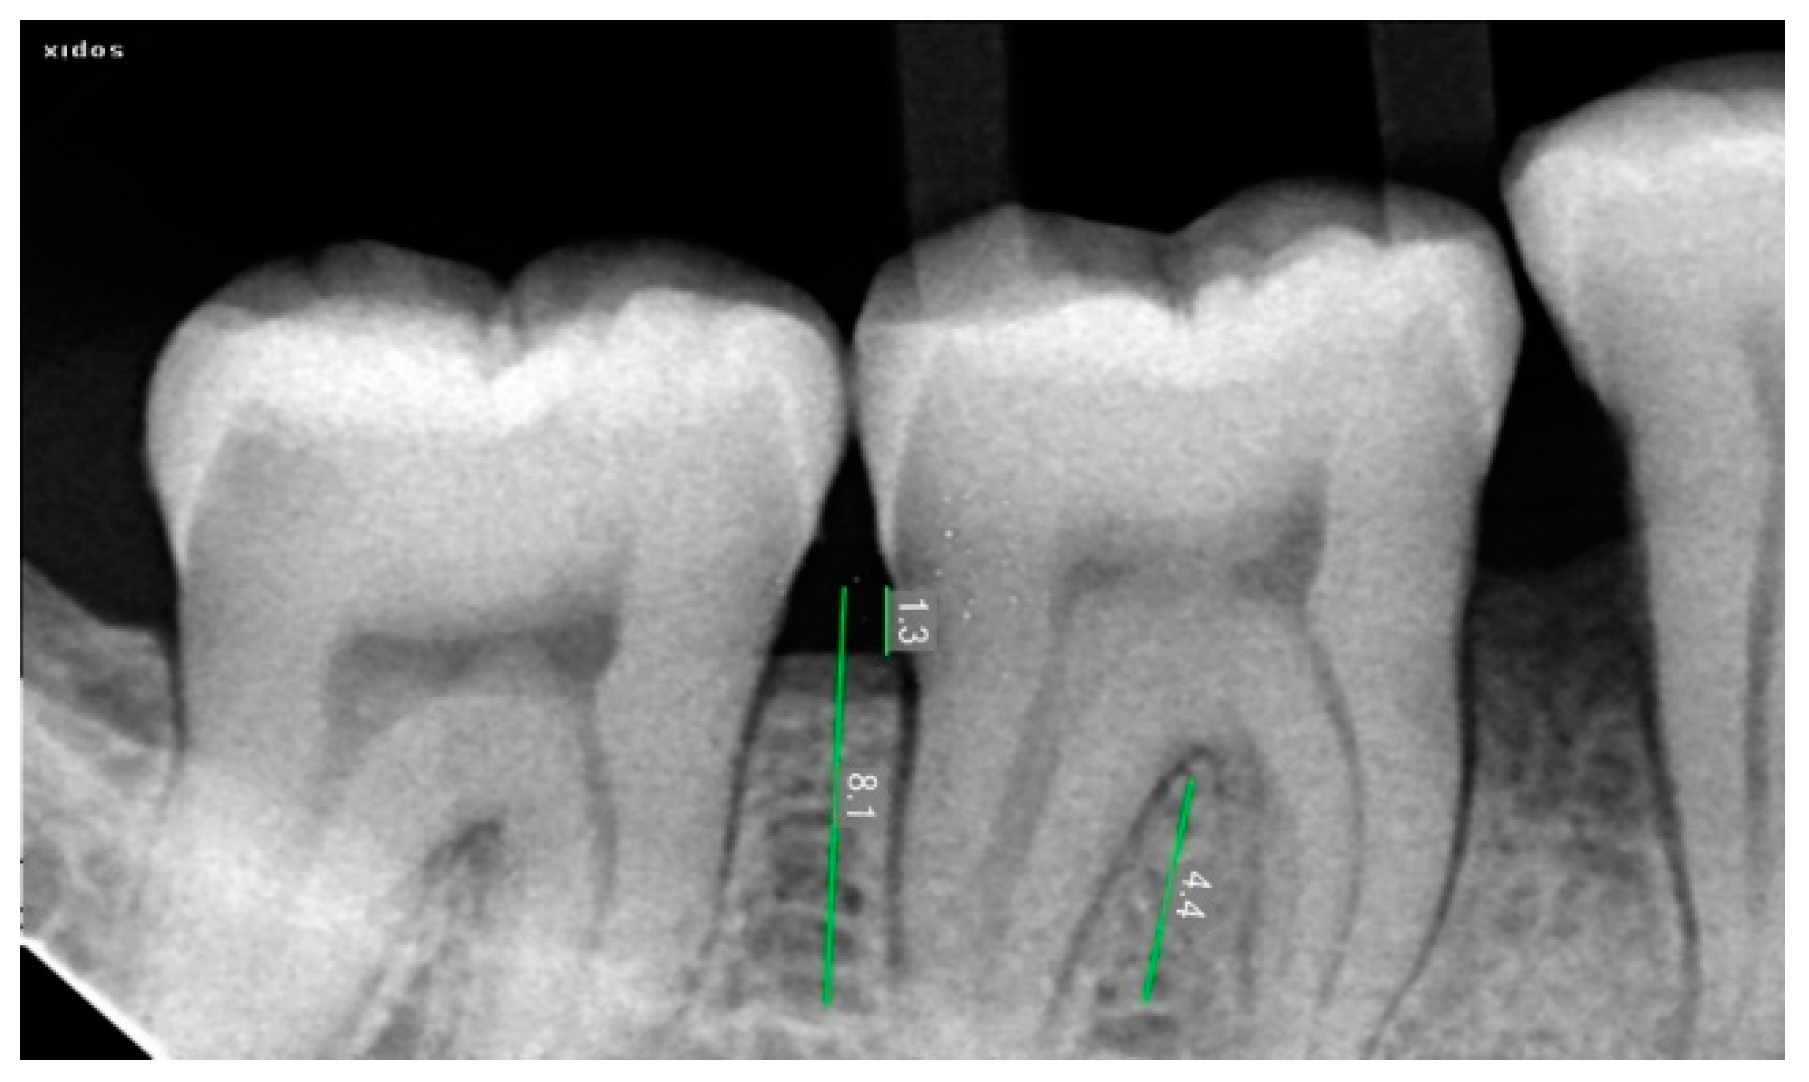

2.3. Radiographic Assessment

| Defect Fill (Mean ± SD) | |

|---|---|

| AM + NB | 1.25 ± 0.38 mm |

| BM + NB | 2.64 ± 0.44 mm |

| p value | 0.0005 |

| AM + NB | 16% |

| BM + NB | 33% |